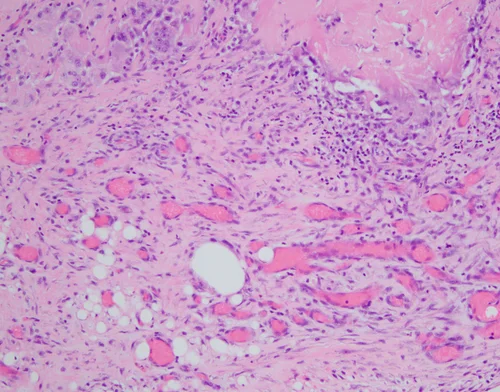

Biopsy Site Change, Fat Necrosis

In fat necrosis we see partially necrotic adipose tissue with interspersed plump, foamy macrophages, multinucleated giant cells, and chronic inflammatory cells. Hemosiderin pigment deposits, fibrosis, and calcification may be present.

On higher power, we see necrotic adipocytes with interspersed foamy macrophages.